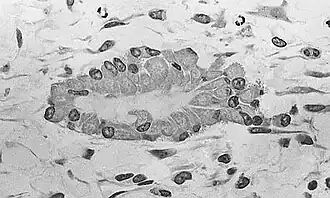

![]() Osteoblasts (purple) rimming a bony spicule (pink - on diagonal of image). In this routinely fixed and decalcified (bone mineral removed) tissue, the osteoblasts have retracted and are separated from each other and from their underlying matrix. In living bone, the cells are linked by tight junctions and gap junctions, and integrated with underlying osteocytes and matrix H&E stain. | |

Hematoxylin and eosin staining (H&E) shows that the cytoplasm of active osteoblasts is slightly basophilic due to the substantial presence of rough endoplasmic reticulum. The active osteoblast produces substantial collagen type I. About 10% of the bone matrix is collagen with the balance mineral.[29] The osteoblast's nucleus is spherical and large. An active osteoblast is characterized morphologically by a prominent Golgi apparatus that appears histologically as a clear zone adjacent to the nucleus. The products of the cell are mostly for transport into the osteoid, the non-mineralized matrix. Active osteoblasts can be labeled by antibodies to Type-I collagen, or using naphthol phosphate and the diazonium dye fast blue to demonstrate alkaline phosphatase enzyme activity directly.

Light micrograph of decalcified cancellous bone displaying osteoblasts actively synthesizing osteoid, containing two osteocytes